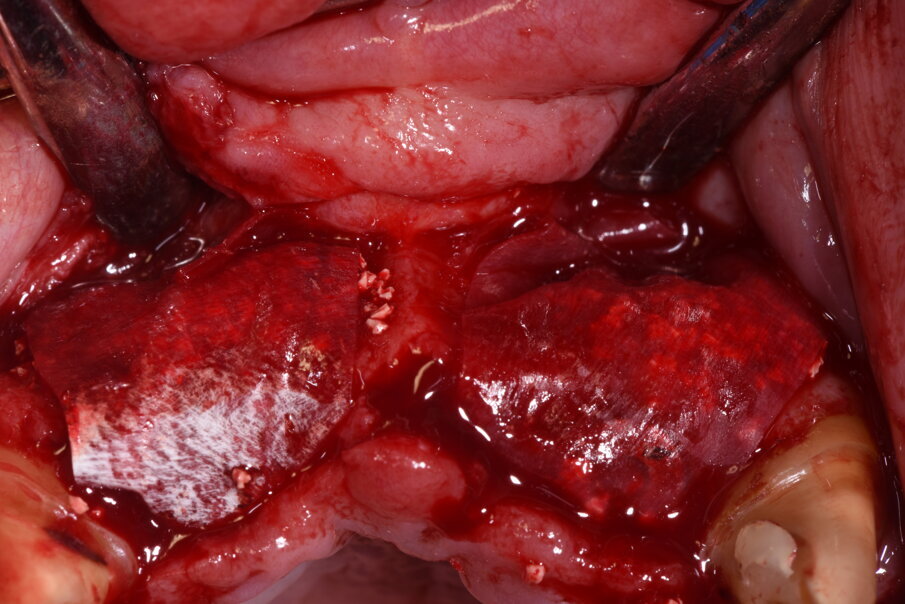

La rigenerazione ossea è stata ottenuta secondo l’impiego di biomateriale di origine bovina demineralizzato e stabilizzato con una membrana a lento riassorbimento in pericardio nativo fissata con dei chiodini in titanio (Fig. 23). Com’è noto la stabilità dell’innesto è un requisito indispensabile per ottenere una reale rigenerazione ossea stabile nel tempo. Dopo 4-6 mesi si effettua una radiografia di controllo eseguendo successivamente un opercolo perimplantare. In questo caso data la lieve deiscenza presente si è optato per l’impiego di un diatermocoagulatore per limitare il danno biologico ai tessuti limitrofi e mantenere inalterata la rivascolarizzazione della sede, inoltre non essendo un materiale metallico ma bensì ceramico, l’eventuale contatto viene disperso e non assorbito dall’impianto (Fig. 24). Data l’ottima stabilizzazione funzionale e volendo contenere i costi viene realizzata un’impronta digitale dell’arcata col primo provvisorio in situ e alla sua rimozione un’impronta dell’intera arcata con e senza gli scan body implantari (Fig. 25). Per mantenere l’opercolo ottenuto si utilizzano delle cappette di guarigione sempre in Zirconia che serviranno anche per stabilizzare i tessuti perimplantari (Fig. 26).

Fig. 23_Per ottimizzare l’azione chirurgica a quella estetica abbiamo progettato una rigenerazione ossea volta ad aumentare il volume vestibolare, utilizzando un sostituto osseo a lento riassorbimento e delle membrane in periostio sottili e riassorbibili fissate con chiodini non riassorbibili.